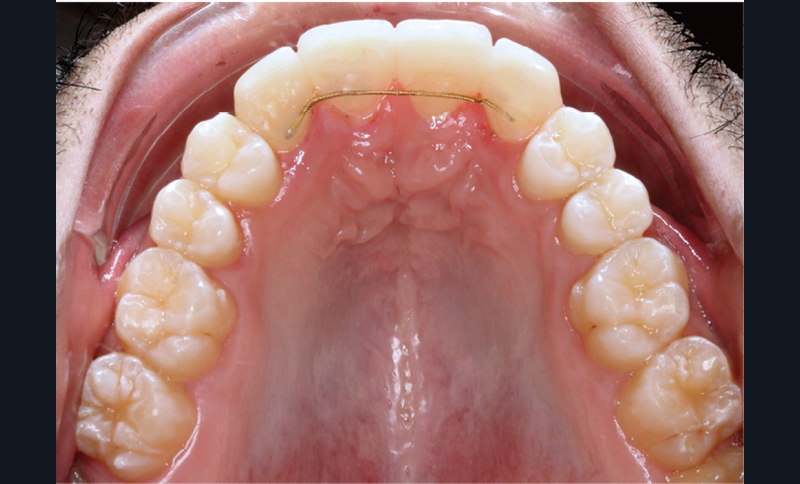

Traitement multi-attaches

Dans un premier temps, l’extraction des 11 et 21 est réalisée. Un bouton est collé sur la 13, visible dans l’alvéole de la 11 afin de permettre sa désinclusion (fig. 2). La traction se fait à l’aide d’un arc TMA .016 x .022 en overlay afin d’avoir un axe de traction horizontal et vestibulaire évitant une résorption de la 12 à cette étape (fig. 3a,b) [3]. Ne pouvant pas mettre d’arc de Nance du fait de la position palatine des incisives latérales, il est convenu que des minivis d’ancrage peuvent être nécessaires si une perte d’ancrage postérieure est constatée (ce qui n’est pas le cas).

Une fois la 13 à l’aplomb de son alvéole, une traction verticale de cette dent peut être réalisée. La 12 n’est pas prise en charge avant la correction de la transposition afin de limiter le risque de résorption de cette dent. La difficulté est alors la gestion des torques antérieurs perturbés, liés aux déplacements réalisés.